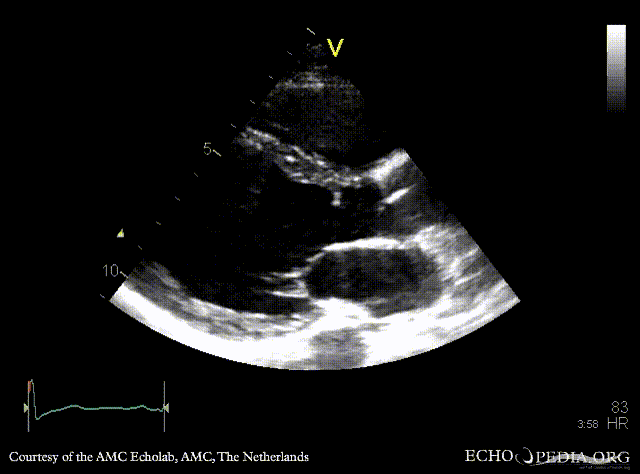

Subvalvular membrane

PSAX: subvalvular membrane PSAX: subvalvular membrane, zoom